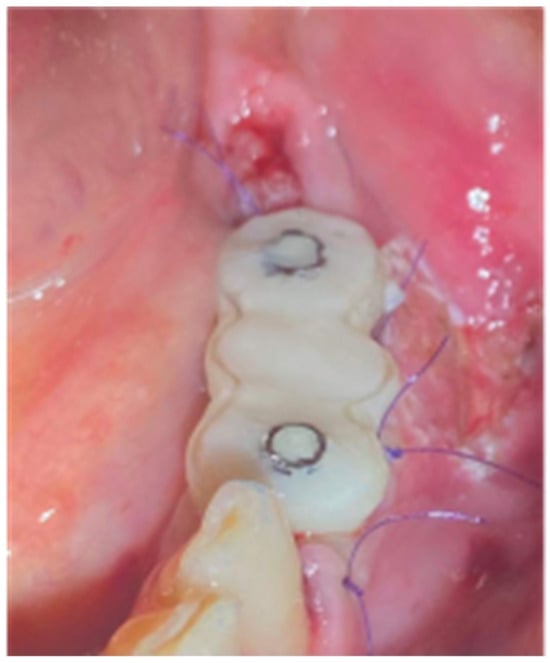

- A palatal incision parallel to the alveolar ridge and located apically nearly 15 mm from the marginal palatal soft tissue, leaving the periosteum intact, was performed prior to the placement of sutures. Then, a split-thickness preparation below the palatal flap was performed until the dissected area reached the incision limits. After confirmation of the communication between both entries, the palatal flap coronal advancement was possible, ensuring a primary closure.

- An intermediate layer of horizontal mattress monofilament absorbable Glycolon 4.0 adaptation sutures (Resorba, Nuremberg, Germany) was placed below the muco-gingival line to secure an additional stabilization of the cortical barrier on both the buccal and the palatal side and the coronal advancement of both flaps.

- A superficial layer of vertical mattress (placed at the papillary areas between the teeth adjacent to the augmentation site), along with simple interrupted Glycolon 5.0 (Resorba, Nuremberg, Germany) closure sutures (placed at the inter-proximal abutment areas), provided primary flap closure and papilla stabilization on their initial pre-operative position.

- A superficial incision, performed with a 15 blade deep in the vestibule, was finally used to reduce muscle pulling during the post-operative healing period.